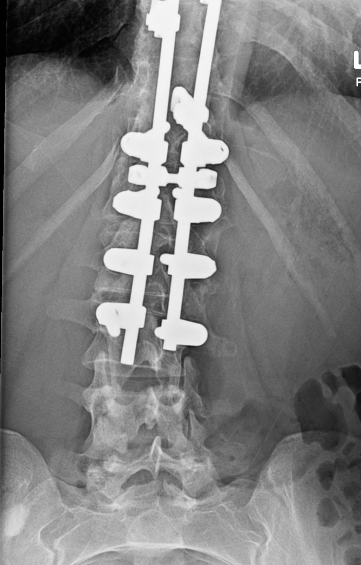

Seems like her epidural space should be intact after this Harrington Rod type procedure she had as a teenager, correct? There really is no decompression/lami type element to the procedure it appears...

Would you put a needle in there for SCS or ESI?

Thread catheter at lower interspace or caudal catheter and run some contrast to confirm?

Epidurogram with catheter to assess feasibility, but I'm still not sure what the pain pattern here is.

With the harrington rods, I think the issue is more the lamina hooks or wires causing scarring, making it hard to drive, and taking up space, but her setup doesn't look like it has any significant hooks above T11.